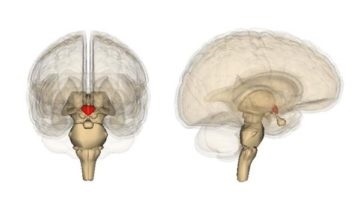

Ahol van. Nem található körülbelül a közepén a koponya alján az agy felületén. Ezen a ponton az alapja a koponyacsontok is egy speciális mélyedés, ez az úgynevezett török nyereg.

Orvosi tény. Agyalapi mirigy súlya mindössze fél gramm. A méretei a test gyakorlatilag független a sex / személy kora.